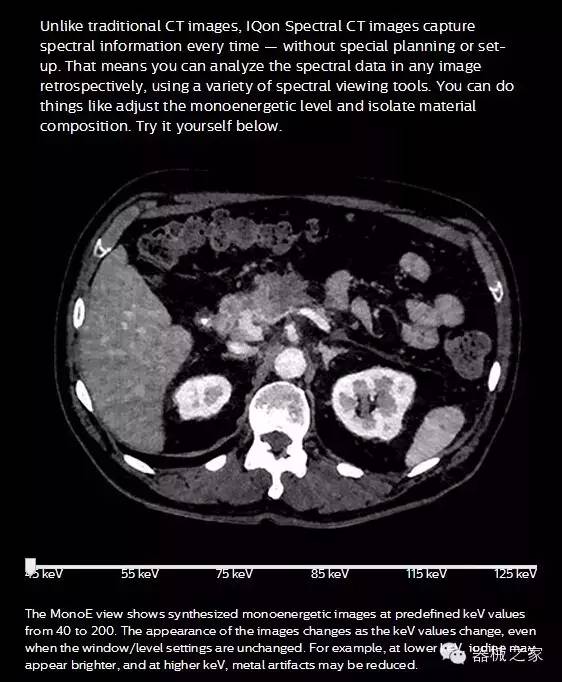

IQon光譜CT能夠按照需求提供光譜量化和工具,并能通過簡單工作流程、在低劑量下對(duì)結(jié)構(gòu)進(jìn)行定性分析

IQon光譜CT -- 是業(yè)界首臺(tái)以探測(cè)器為成像基礎(chǔ)的光譜CT,它可以在單次常規(guī)掃描下獲得傳統(tǒng)解剖影像及光譜功能影像。不僅可以提供精準(zhǔn)的診斷信息,還可簡化工作流程、在低劑量下完成定量與定性分析。